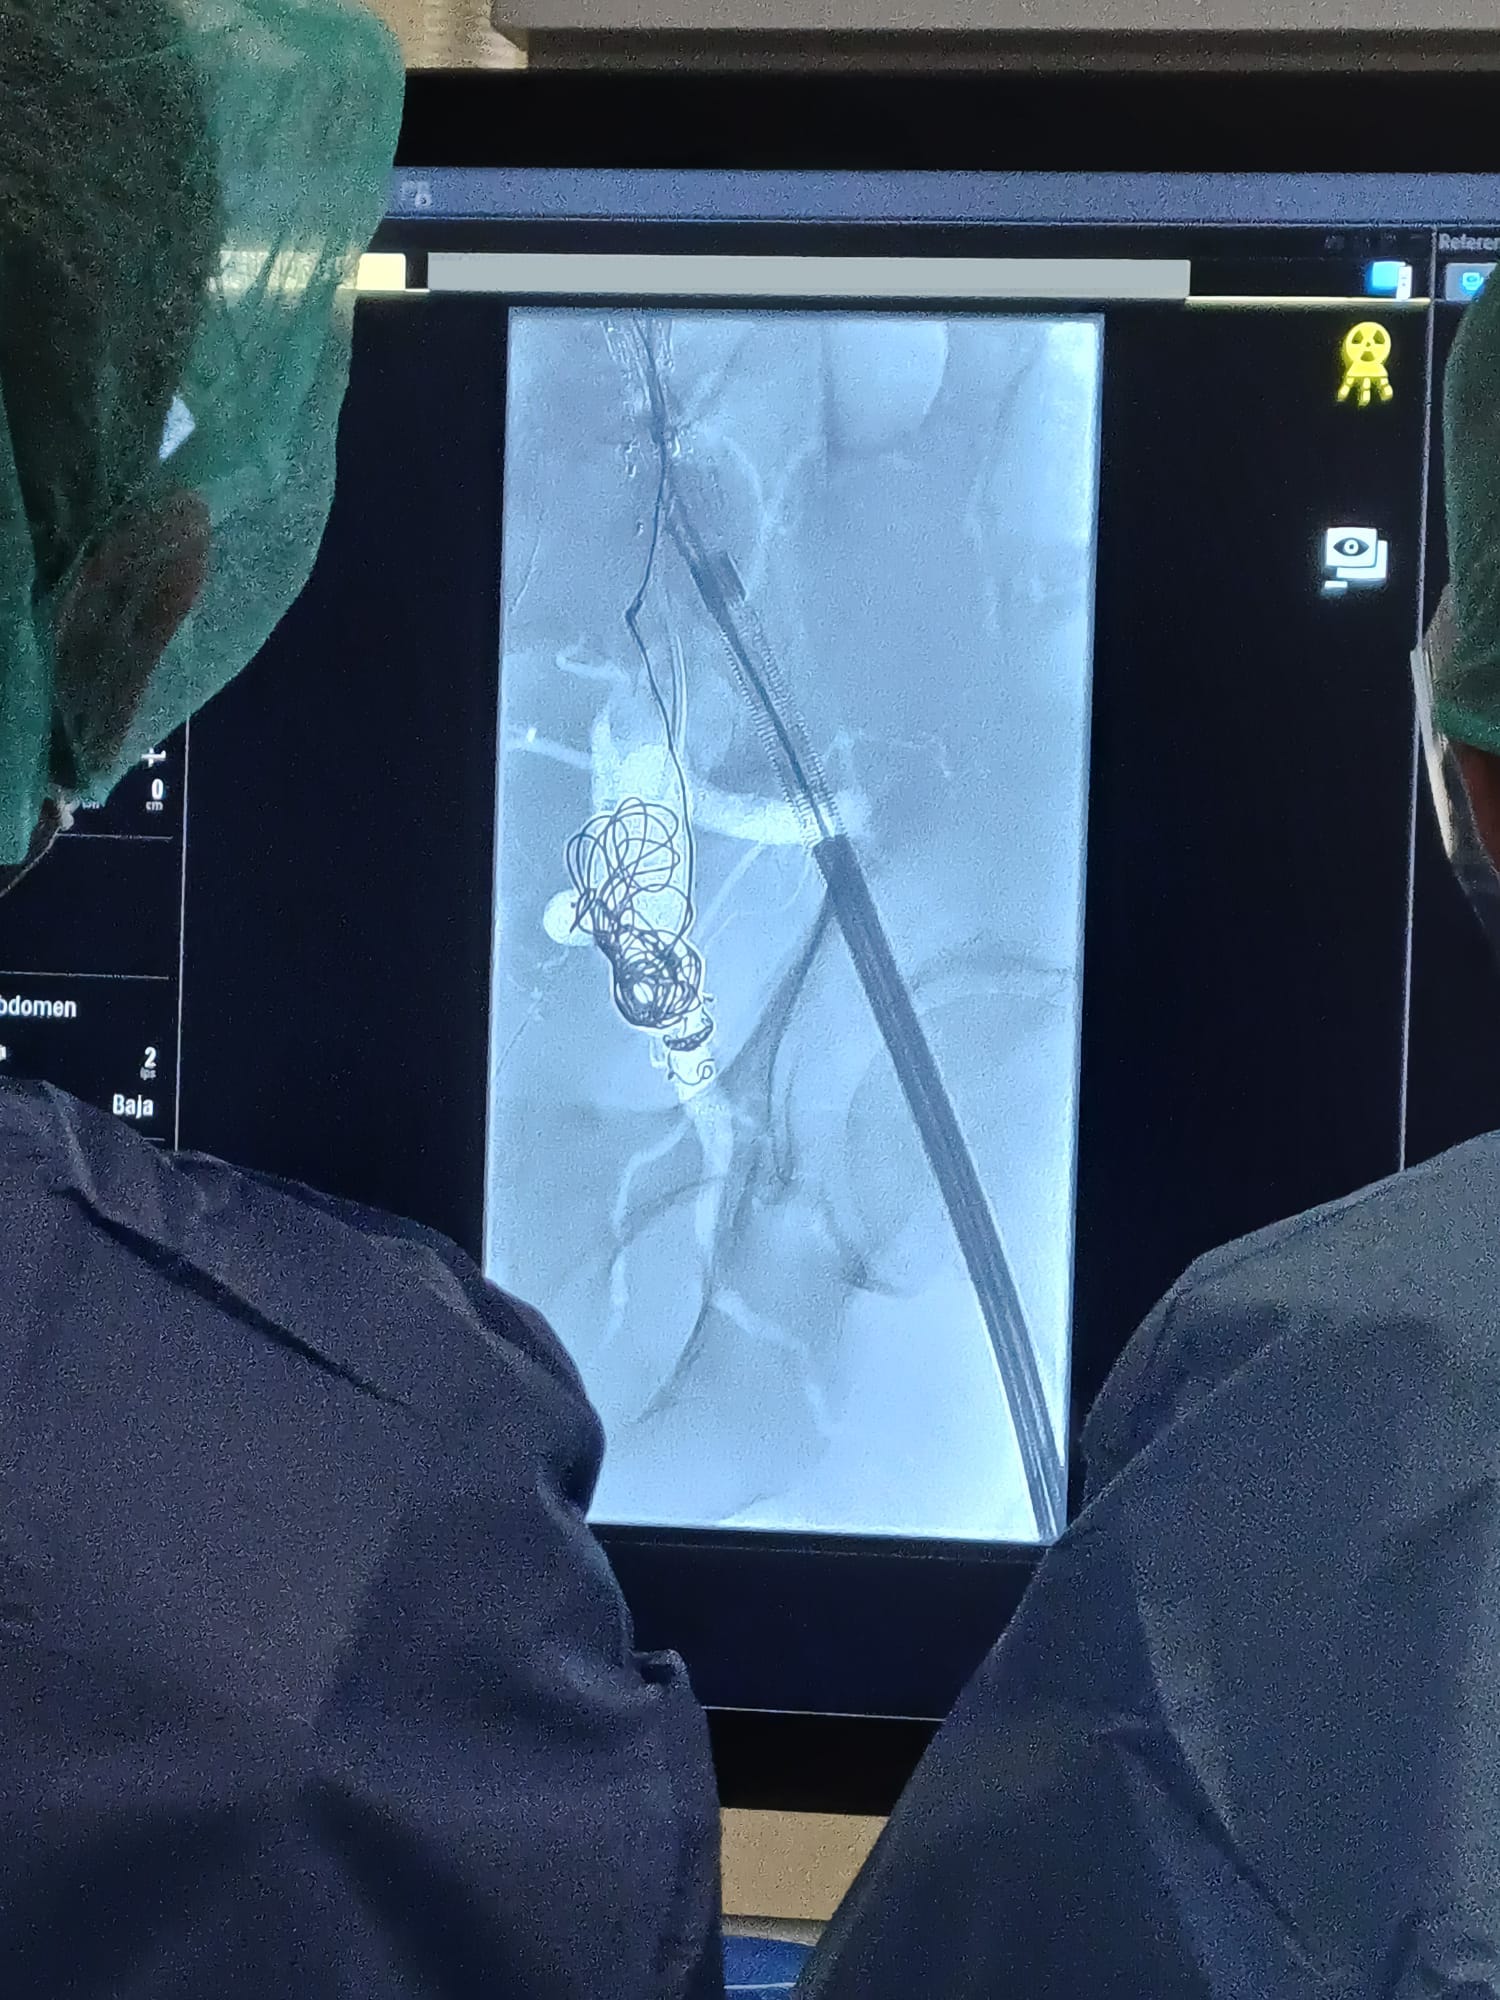

Radiología Vascular Intervencionista y Cirugía Endovascular

Dispositivos de última generación para el tratamiento endovascular de patologías vasculares periféricas y aórticas. Amplio catálogo de stents, endoprótesis, balones, catéteres de cruce, guías y accesorios para procedimientos mínimamente invasivos en sala de hemodinámica y quirófano vascular.

Stents Endoprótesis Catéteres Coils

Soluciones avanzadas para radiología intervencionista y quirófano híbrido. Incluye sistemas de fluoroscopia, arcos en C quirúrgicos y angiógrafos de última generación para procedimientos complejos. Equipamiento diseñado para salas de intervencionismo, cirugía vascular y hemodinámica, garantizando la máxima precision con la mínima dosis de radiación.

Angiógrafos Arcos en C Fluoroscopia